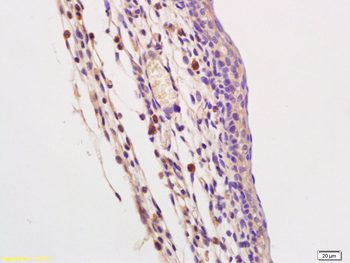

FC, ICC, IF, IHC-Fr, IHC-P

应用稀释比例:IHC-P=1:100-500, IHC-F=1:100-500, ICC/IF=1:100-500, IF=1:100-500, Flow-Cyt=1μg /test